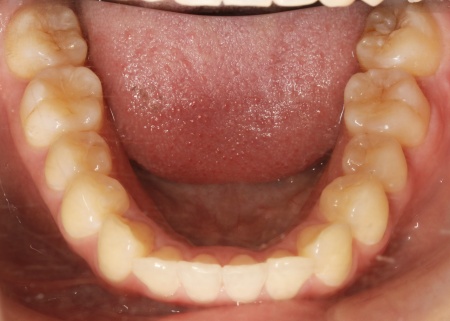

治療後